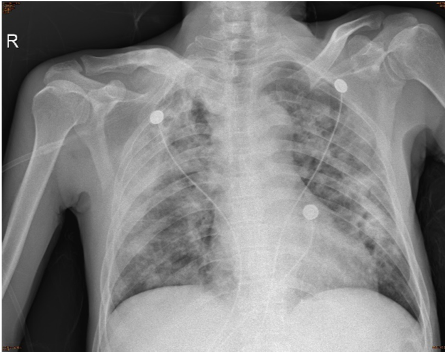

青少年女性,无发热,以咳嗽、咳痰为主要症状,伴有鼻塞、流涕等鼻窦炎表现,病程中查血象白细胞及分类正常,头孢类抗菌药物治疗无效,胸部 CT 提示左下肺斑片状高密度影,纵隔窗可见实变影,需要考虑非典型病原体肺炎可能。